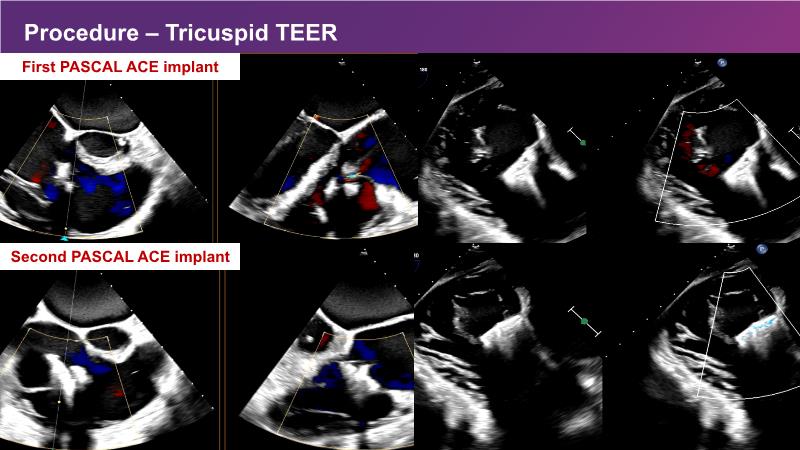

This session explores the features of the PASCAL Precision and the EVOQUE tricuspid replacement systems through simulators and case presentations, while a panel of experts discuss the technology, witnessing live demonstrations of treating mitral and tricuspid regurgitation patients.

- To learn about the differentiating features of the PASCAL Precision system showcased in a series of simulators alongside case presentations

- To interact with a panel of experts discussing the PASCAL Precision system technology and showcasing, live, its different key features in action and how they help treat mitral regurgitation and tricuspid regurgitation patients